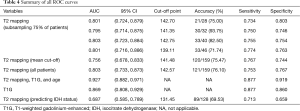

Table 3 and Figure 3 show the median T2 relaxation times and comparisons between molecular categories. The T2 relaxation time distribution was significantly different between IDH-mt and IDH-wt gliomas (P=0.001) and between MGMT-methylated and MGMT-unmethylated gliomas (P=0.03). Borderline significance was found between 1p/19q-codeleted and not co-deleted gliomas (P=0.05). No distribution difference was observed between ATRX gene loss and present gliomas; however, when T2 relaxation times were used as a diagnostic tool to predict molecular category, they could not make accurate predictions, with all AUCs were between 0.5–0.7. Table 4 shows the ROC analysis for predicting the IDH status, with an AUC of 0.687.

In WHO grade II glioma, the T2 relaxation time of the solid tumor region was higher than that of HGG. The mean cut-off point between WHO grade II glioma and HGG was 141.48 ms. Figure 4 shows ROC curves of T2 mapping, each built with the randomly selected 75% of cases. The AUC of these curves were 0.801, 0.795, 0.803, and 0.801. The cut-off points from these curves were then used to test the accuracy of T2 mapping on the remaining 25% of the cases; the accuracy was 21/28 (75%), 30/32 (93.75%), 33/40 (82.50%), and 33/46 (71.74%). Table 4 summarizes the main findings of the ROC curves.

Multivariable ROC

The multivariate binary logistic regression model included variables of age, enhancement status, and T2 relaxation. Gender was not included in the multivariate model as it did not show statistical significance in the univariate regression model. The AUC of the multivariable ROC curve was 0.927 (95% CI: 0.882–0.971). For diagnosis based on enhancement status, the AUC was 0.869 (95% CI: 0.808–0.929), which was not significantly higher than the AUC for diagnosis based on T2 mapping. Figure 4 shows the multivariable ROC curve and the ROC curve for diagnosis based on enhancement status.

We conducted a single-center, retrospective diagnostic study to explore the diagnostic performance of T2 mapping in differentiating WHO grade II glioma from HGG. T2 mapping appeared to be an appropriate diagnostic tool (AUC, 0.803; sensitivity, 0.753; specificity, 0.767), especially when used combined with patient age and glioma enhancement status data (AUC, 0.927; sensitivity, 0.877; specificity, 0.919). Study data showed that gliomas with short T2 relaxation times were likely to be HGGs, and gliomas with long T2 relaxation times were likely to be WHO grade II gliomas. Median T2 relaxation time was also significantly different between different molecular categories; specifically, IDH-mt gliomas had longer T2 relaxation times than IDH-wt gliomas. T2 mapping is non-invasive and requires no contrast agent, making it a viable prospect for pre-operative diffuse glioma grading.